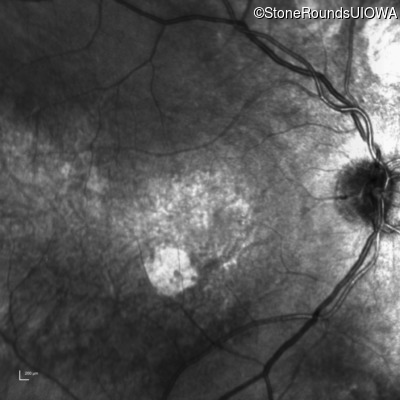

Infrared Fundus Photograph - Left - 20/125

Exemplar